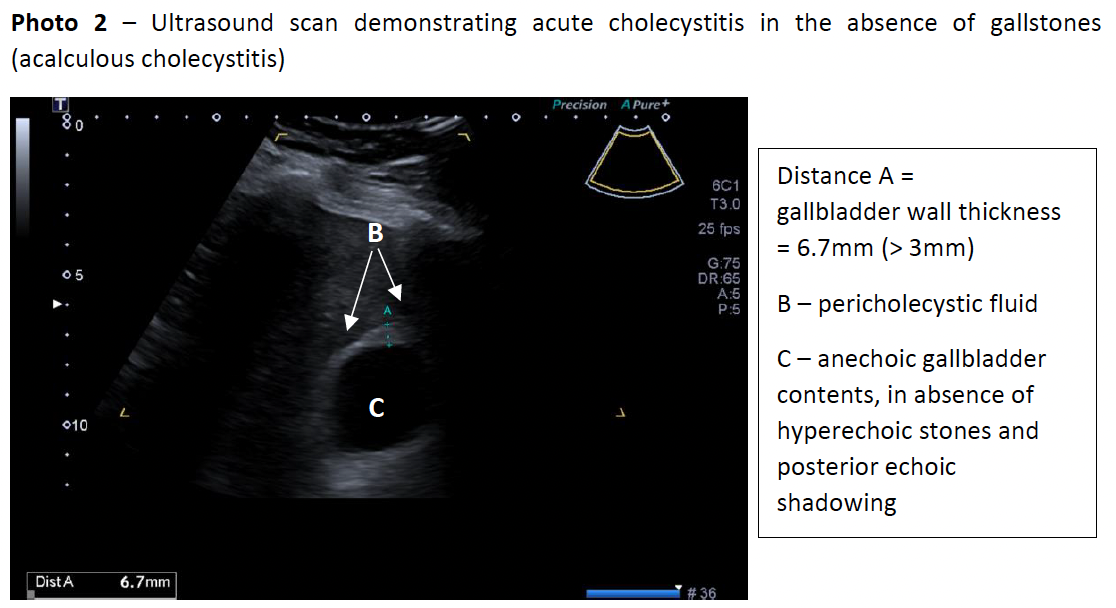

The patient’s bloods showed a lactate of 2.0mmol/L, white cell count of 14.0x109/L, normal electrolytes/urea/creatinine, slightly elevated total bilirubin of 24μmol/L but otherwise normal liver function tests. A computed tomography of the abdomen and pelvis (CT-AP) was performed which demonstrated pericholecystic free fluid and a mildly thickened gallbladder wall and normal common bile duct diameter (3mm), in keeping with acute cholecystitis in the absence of radio-opaque gallstones (photo 1). An abdominal ultrasound (photo 2) the next day confirmed CT findings with no gallstones seen, indicating AAC.